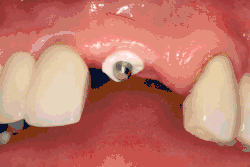

Разборный имплантат состоит из непосредственно имплантата и надстройки (супраструктуры), именуемой абатментом. Такой имплантат может быть установлен по одно- и двухэтапному протоколу. Двухэтапный протокол подразумевает полное погружение имплантата и накрывание его слизистой оболочкой, в результате чего исключается любой контакт имплантата с полостью рта — эта процедура называется первым этапом дентальной имплантации. Второй этап заключается в установке какой-либо надстройки (супраструктуры) — это может быть как формирователь десны, так и абатмент с временной коронкой или другим видом протезной конструкции. После какого промежутка времени будет выполнен второй этап обычно решает имплантолог, опираясь на данные о качестве костной ткани, возраст и общее состояние пациента, а также свой клинический опыт. Классические сроки составляют 4—6 месяцев, однако последнее время существует тенденция к сокращению сроков ожидания до 2,5—3 месяцев. Это связано с лучшим пониманием процесса остеоинтеграции, а также оптимизацией макродизайна и микрохарактеристик поверхности имплантатов.

В неразборном имплантате (употребляются также термины: одноэтапный имплантат, моноимплантат) внутрикостная часть имплантата и абатмент обычно изготовлены из единого куска материала. После установки имплантат своей наддесневой частью сразу оказываются в контакте с полостью рта. На усмотрение доктора устанавливается формирователь десны либо временная коронка. В случае установки временной протезной конструкции (коронки, моста или полного протеза) на имплантат не позднее трёх дней после имплантации говорят о немедленной нагрузке.